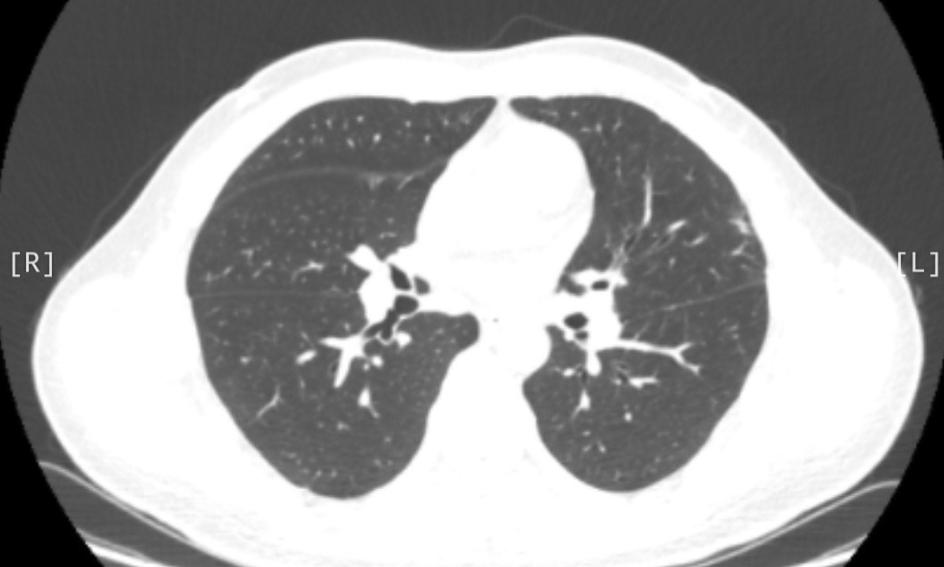

换了药后,肺结节就消失了!44岁的男性,在今年4月底查出肺部有个部分实性结节,吃了点消炎药没见好,5月初再拍CT,发现结节居然还长大了! 他当时就急了,火急火燎赶到门诊,担心是不是要转移了,催着我赶紧安排手术。 我仔细看了他的片子,从形态上看,更像是炎症,不像肿瘤。所以还是劝他先别急着开刀,建议他换一种抗感染药再试试,也鼓励他放宽心,按时复查。 结果最近他来复查——原来的病灶明显吸收了!说明这确实就是个炎症,之前只是药没用对。 真是替他高兴!他们夫妻俩不停说谢谢,开开心心回家了。 我经常说一句话:“肺结节别轻易开刀”。虽然我是胸外科医生,主要就是做手术的,但还是经常劝大家要冷静,能不切先不切。 现在很多人一查出肺结节就紧张得不行,吃不下睡不着,总觉得切掉就没事了。但实际上,如果没必要做手术,这一刀下去,肺功能可能会受影响,有的人术后还会长期咳嗽、胸痛,其实挺受罪的。 事实上,大多数肺结节都是良性的,真正是恶性的比例很低,大概只有5%-10%。而且即便是恶性,很多也发展得非常慢,定期观察很安全。哪怕后来真有变化,到时候再做手术,效果也是一样的。 所以,查出肺结节先别慌,找专业医生看清楚,很多时候真的不必急着那一刀。[玫瑰][谢谢]胸外科乔贵宾医生肺结节[超话]